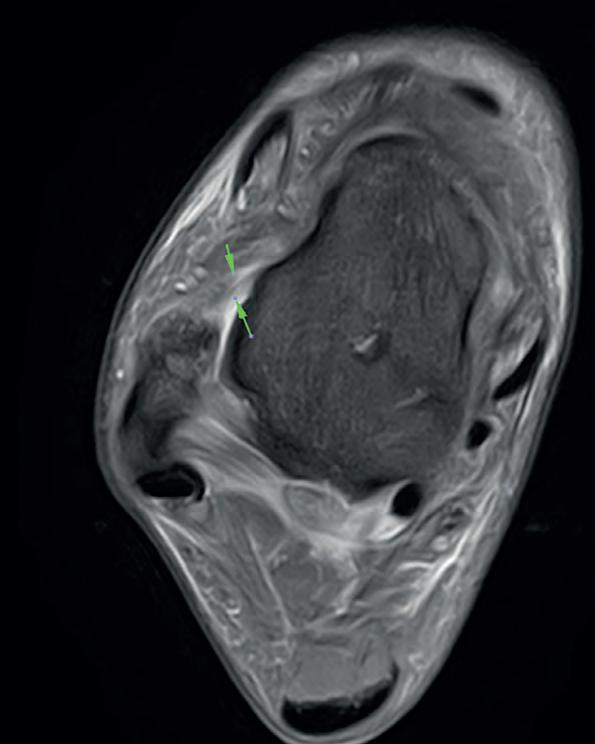

By using ultrasound, CT or MRI, we can see the extent of commonly occurring (Fig 2) or unique injury on site within our dedicated Medical Imaging Centre4 at the Manchester United Carrington Training Centre without any of the confidentiality issues of transferring a patient to a local hospital. Figure 3, for example, shows a T2 weighted image of the coronal view of the right knee showing an acute pivot shift injury with an acute lateral condylar bony contusion which is highly indicative of an associated ACL tear. The female athlete was examined using a Canon Medical Vantage Galan 3T MRI.

Fig 2: Canon Medical Vantage Galan 3T MRI acquired Axial PD Fat Supressed image of the right ankle demonstrating a grade 1/2 tear of the anterior talofibular ligament (ATFL).

Fig 3: Coronal PD Fat Saturated image of the right knee showing an acute pivot shift injury with an acute lateral condylar bony contusion, which is highly indicative of an associated anterior cruciate ligament (ACL) tear acquired using Canon Medical Vantage Galan 3T MRI.